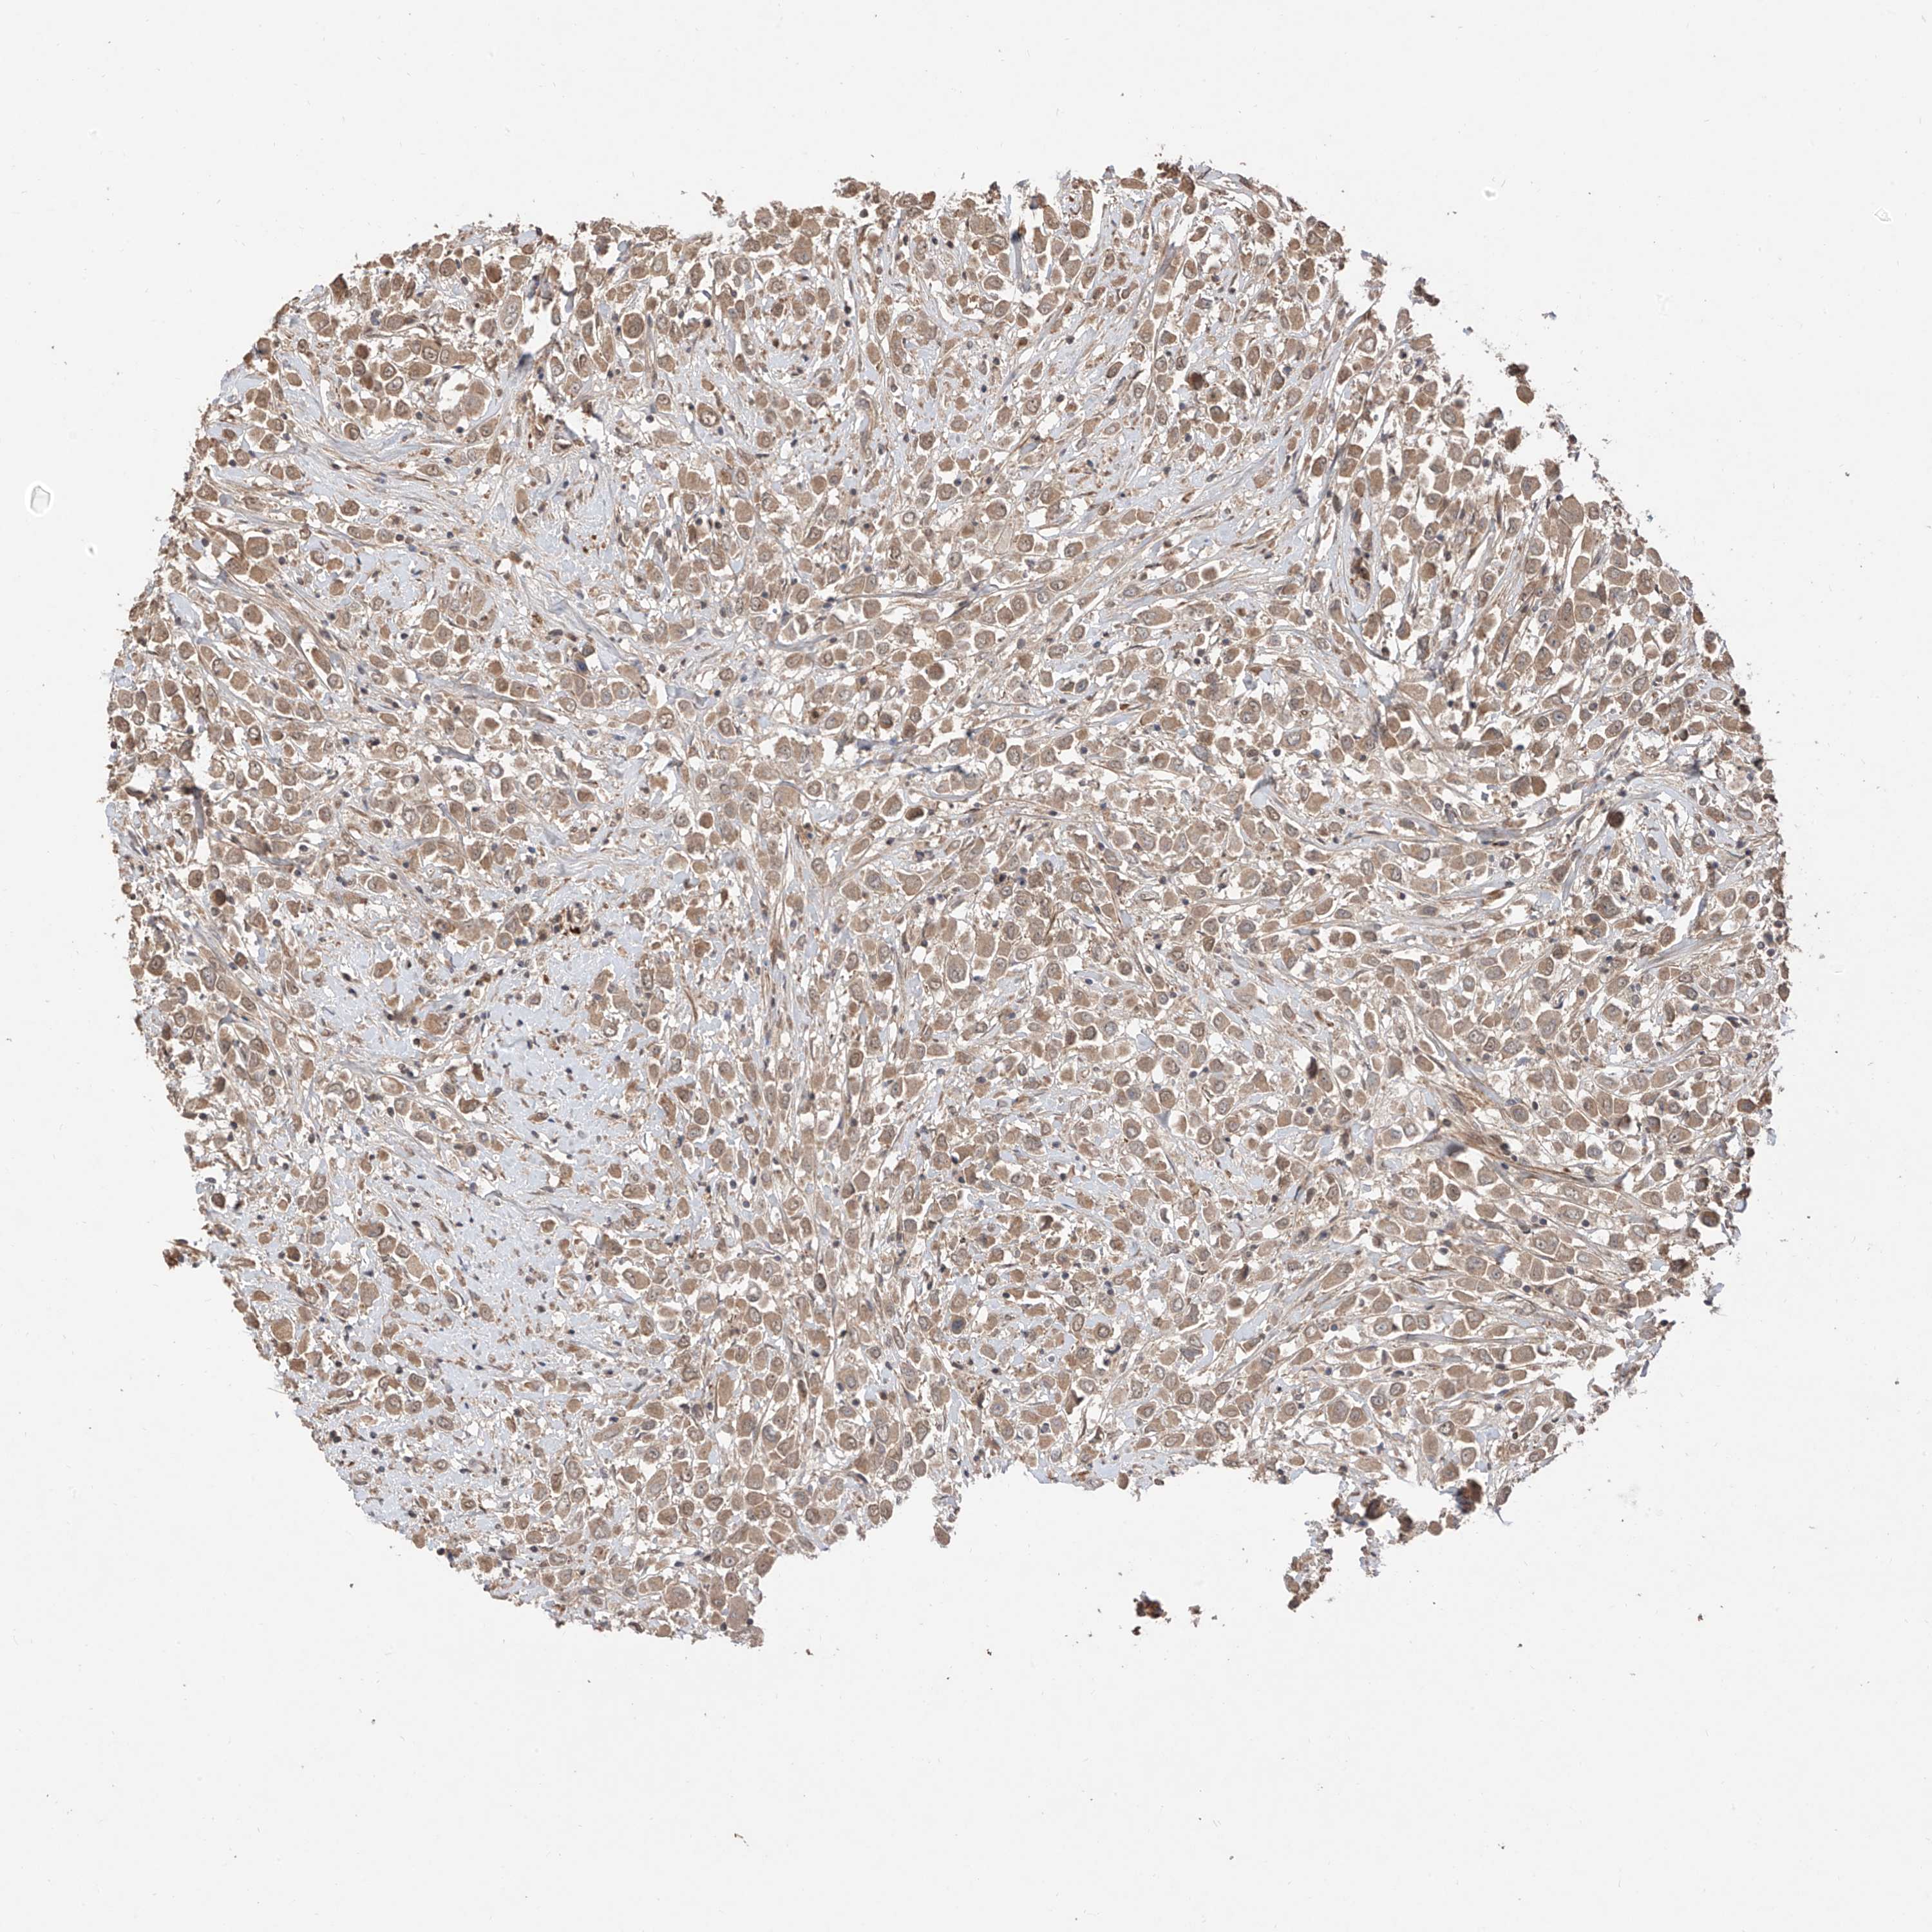

CANCER BREAST CANCER Show tissue menu

BRCA TCGA BRCA VALIDATION PROTEIN EXPRESSION